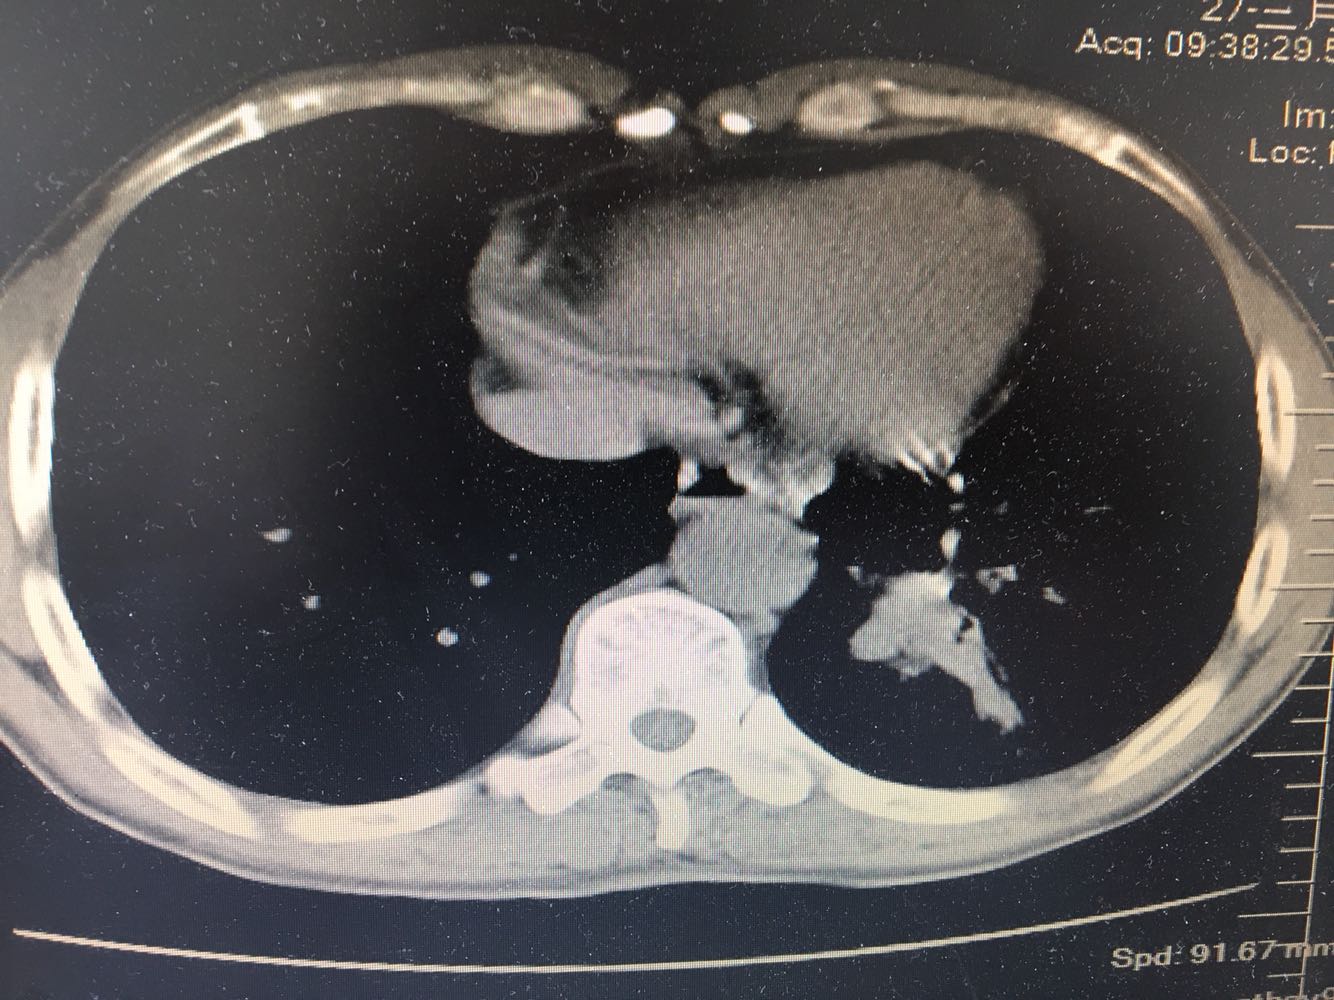

男,63岁,咳嗽1个月入院,患者自述1个月前无诱因咳嗽,阵发性干咳,无痰,时有血丝,无发热,左胸痛,活动后气短,静滴头孢13天无好转,门诊查肺CT后以 肺占位收入我科,病来饮食睡眠可,体重明显下降。既往疝气术后1年,吸烟史30年,每日1包。

左肺癌

左肺中央型肺癌,是否可以手术,还是化疗,放疗,靶向治疗?